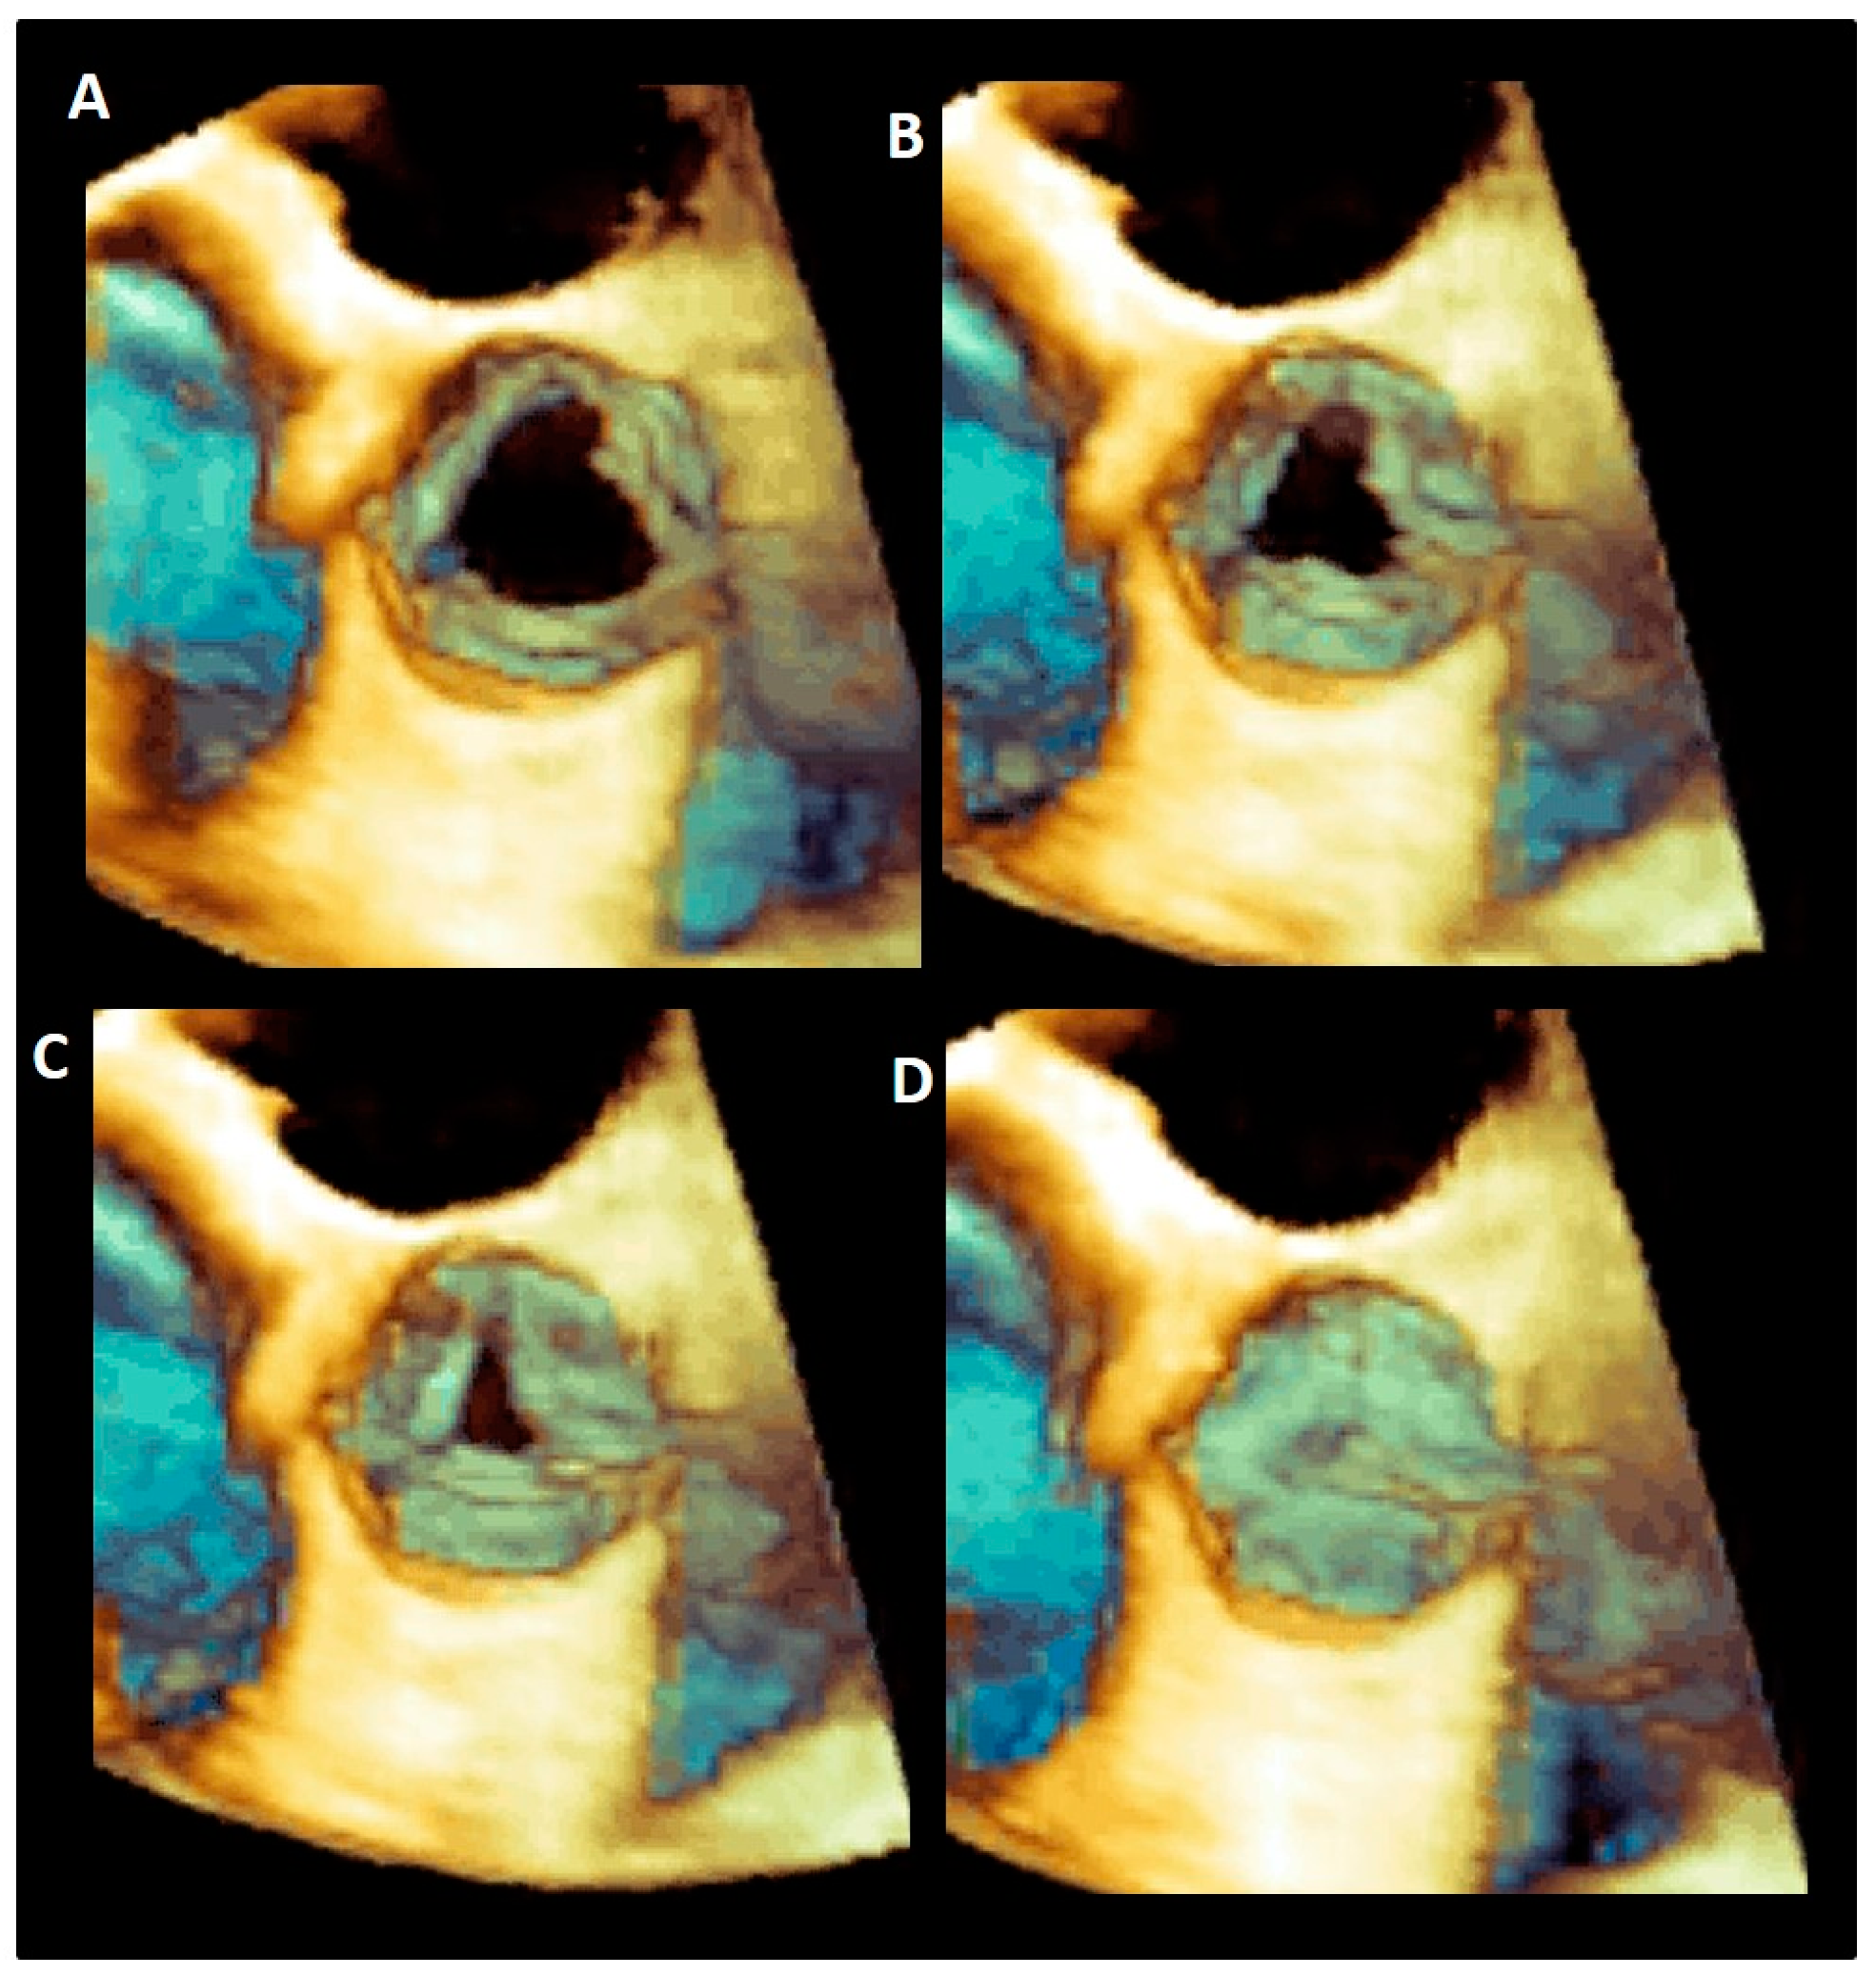

3.8. Leaflets